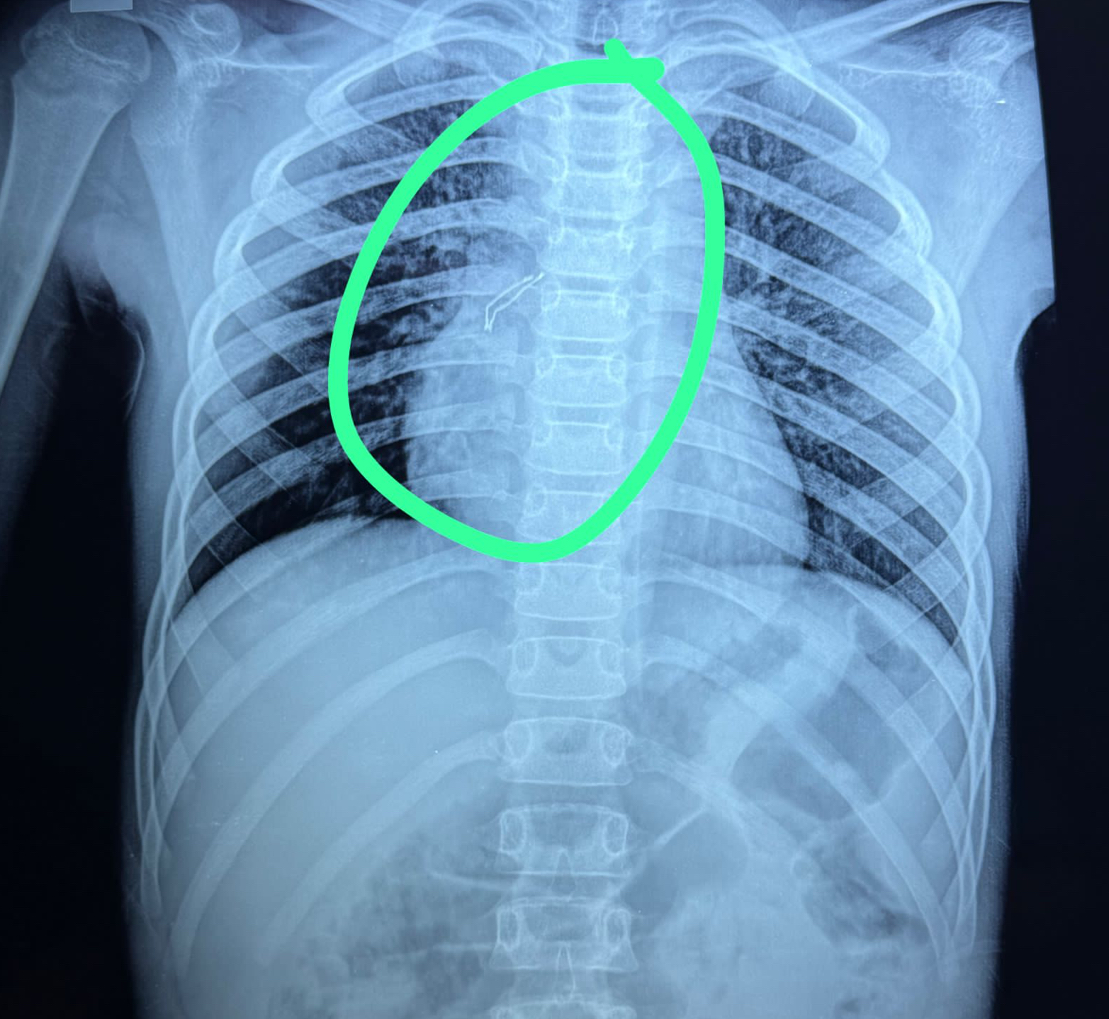

نجح فريق جراحي بمستشفى الأطفال التخصصي بمدينة بنها بمحافظة القليوبية، في إنقاذ حياة طفل يبلغ من العمر 10 سنوات، حيث كان يعاني من صعوبة التنفس، وذلك بعد التنقل بين العديد من مستشفيات القاهرة لإنقاذه، حيث تبين أنه ابتله "لمبة ريموت كنترول"، والتى استقرت بالقصبة الهوائية، وتم استخراج اللمبة بواسطة منظار القصبة الهوائية، وتحسنت حالة الطفل.

وتابعت المستشفى، أنه تم توجيهه إلى مستشفى الأطفال التخصصى ببنها، فحضر ومعه طفله البالغ من العمر 10 سنوات، وقد ابتلع "لمبة ريموت كنترول"، والتى استقرت بالقصبة الهوائية، وعلى الفور تم عمل الأشعات اللازمة، وتجهيز الحالة ودخولها إلى غرفة العمليات، وتم استخراج اللمبة بواسطة منظار القصبة الهوائية، تحت إشراف فريق طبى متخصص على مستوى عالى ومهارة فائقة.